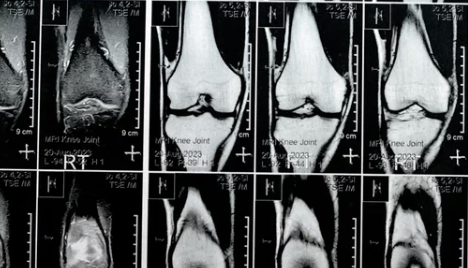

| MRI 검사 | 연골 손상, 인대 파열, 관절 내 염증 확인 |

- 무릎 관절염과 연골 손상 여부를 구별하기 위해 MRI 검사가 효과적입니다.